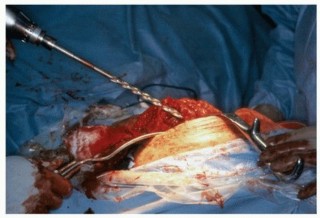

Femoral Preparation

Following acetabular preparation and component insertion, attention is turned to the femur. The femur is elevated and mobilized. Adequate soft tissue release, including release of the gluteus maximus insertion on the linea aspera if necessary, is performed to allow straight-line access to the femoral canal.

The femoral canal is initially opened with a box osteotome or starter awl, ensuring lateralization into the greater trochanter to prevent varus malalignment of the stem.

Distal Preparation: For modular stems utilizing diaphyseal fixation (typically fluted, tapered, or cylindrical distal stems), rigid straight reamers are utilized. Reaming is performed sequentially until cortical chatter is achieved, indicating rigid diaphyseal engagement. The depth of reaming is dictated by preoperative templating and the specific implant design.

Once the optimal trial components are identified, the trials are removed. The final distal stem is impacted into the diaphysis until it achieves a rigid, rotationally stable interference fit.

The proximal body is applied in the exact version determined during trialing. The components are engaged using the manufacturer-specific impaction tool. Multiple firm strikes with a heavy mallet are required to achieve cold welding of the Morse taper.